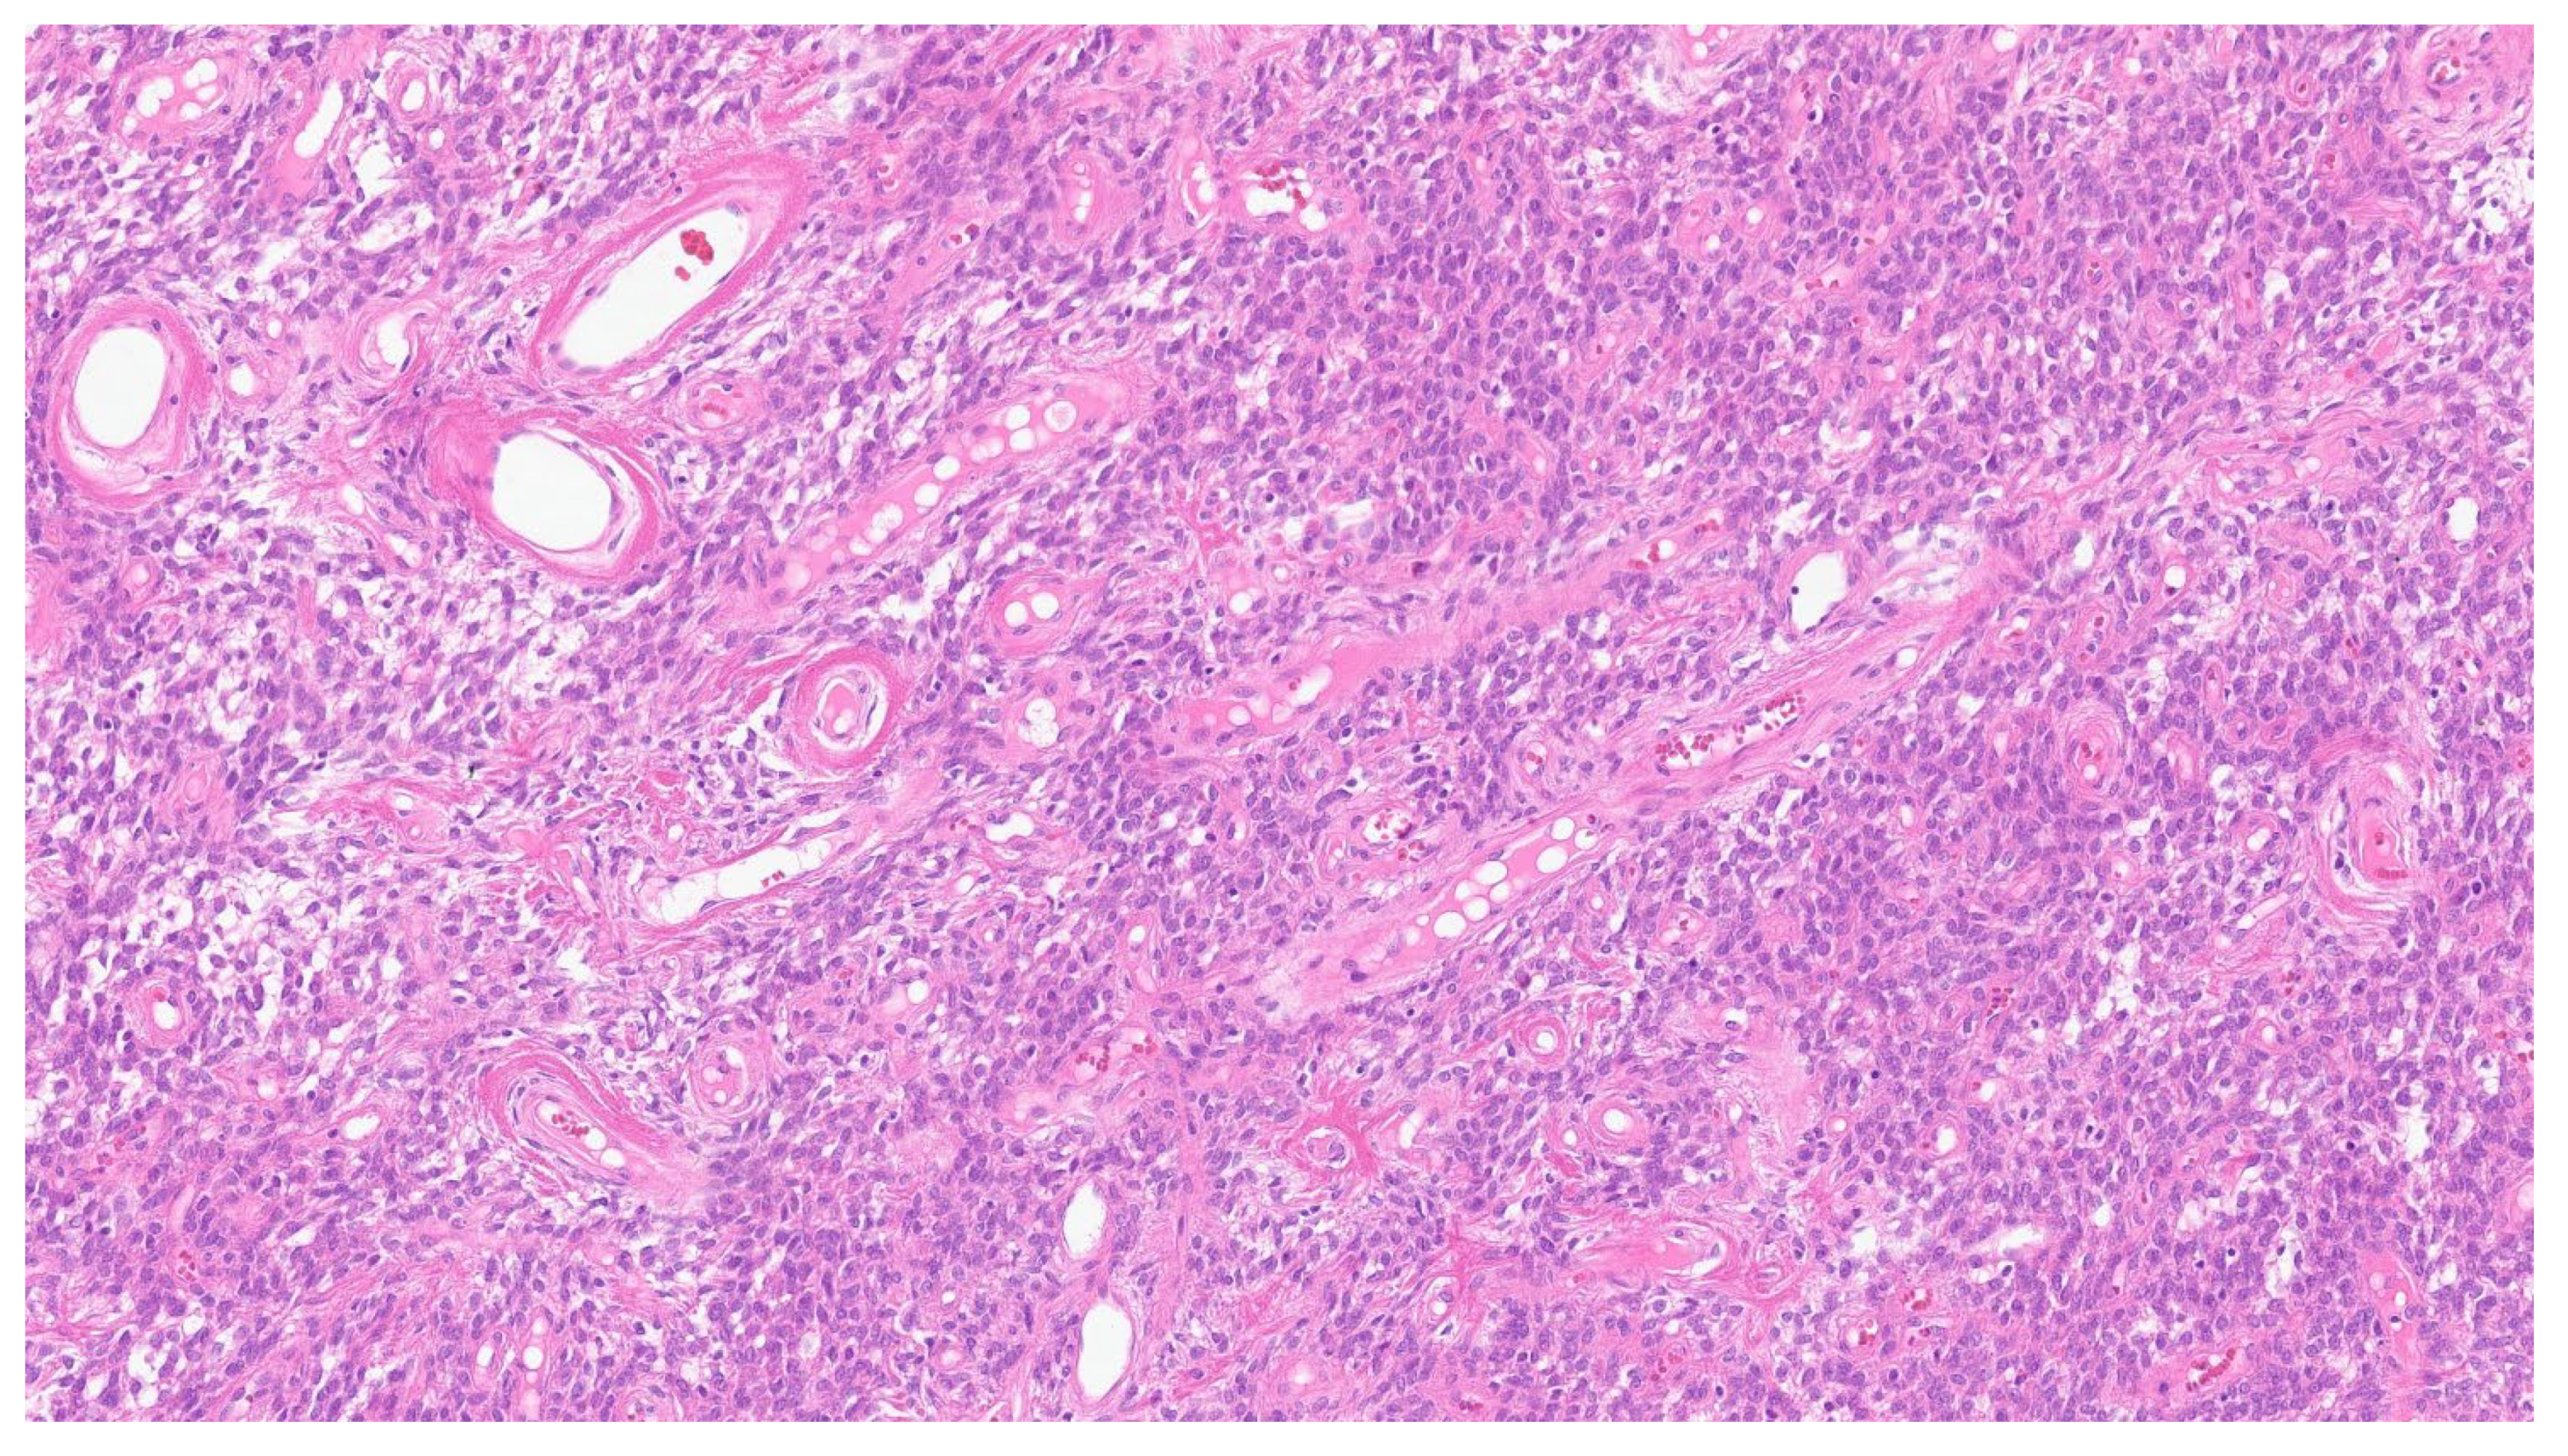

| Inflammatory myofibroblastic tumor | Children and young adults | Colon and small intestine | Variable, from abdominal pain to obstruction | Uniform, plump spindle cells with pale cytoplasm organized into loose fascicles; colagenous or myxoid stroma with inflammation, mainly lymhocytes and plasma cells | α-SMA, ALK positive |

| Fibromatosis | 30 and 40 years | Mesentery of the small bowel | Abdominal pain | Long fascicles of spindle cells with ovoid nuclei without atypia or necrosis | Β-catenin |